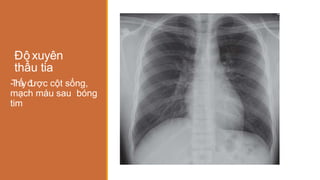

Độ xuyên

thấu tia

ược cột sống,

mạch máu sau bóng

tim